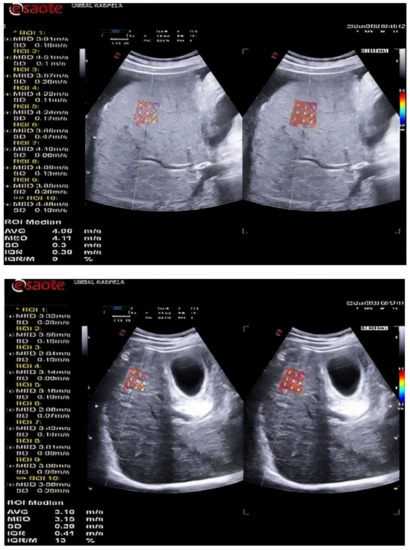

LSM was performed by 2D-SWE using the QElaXto® software, version F104513Q101701 of an Esaote MyLab™ 9 eXP (Genoa, Italy) ultrasound device. A convex C1-8IQ appleprobe transducer was used. Ten elastographic measurements were performed with a validation criterion-median interquartile range (IQR/M) <30% in accordance with current recommendations [5].

LS was assessed elastographically by examining the right hepatic lobe of each patient through the intercostal space. Patients were in a supine position with their right arm at maximum abduction in compliance with the latest requirements for quality measurement [6,7]. During standard B-mode, an assessment area was selected with no large blood vessels. Location at a distance of at least 1.5 cm from the Glisson’s capsule was selected and the ROI size was fixed by the device. The patient was instructed to hold his breath while the values were calculated (Figure 1). If the colour box was not filled by > 50% of its surface or if breathing was uncontrolled, the elastogram was discarded and a new acquisition was attempted. Ten LSMs were obtained, and the median value in m/s was used for analysis.

Figure 1. 2D-SWE images in a patient with liver cirrhosis.